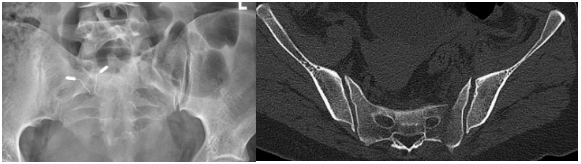

患者焦女士,因车祸伤致全身多处骨折。行骶椎CT检查示: 骶骨左侧骨质连续性中断,断端分离移位。入院后,骨科王建伟主任医师,陈静住院医师对患者病情进行分析,结合患者症状、体征及辅助检查,诊断为:1.骶骨左侧骨折;2.双侧耻骨上下支骨折。因骶骨骨折有分离移位,骨盆不稳。

在征得患者及家属同意后,5月12日,在麻醉手术科团队和影像科团队的配合下,骨科团队顺利开展了CT引导下行经皮螺钉内固定的微创手术。该手术在局部麻醉下采用微创的办法,在患者骶髂部行一约1cm大小切口,切口小、手术时间短、恢复快,患者疼痛感少,能早期行功能锻炼,得到了患者的点赞!